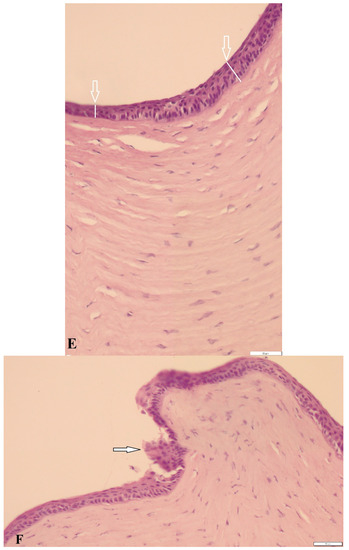

3.3. Histological Findings and Epidermal Thickness